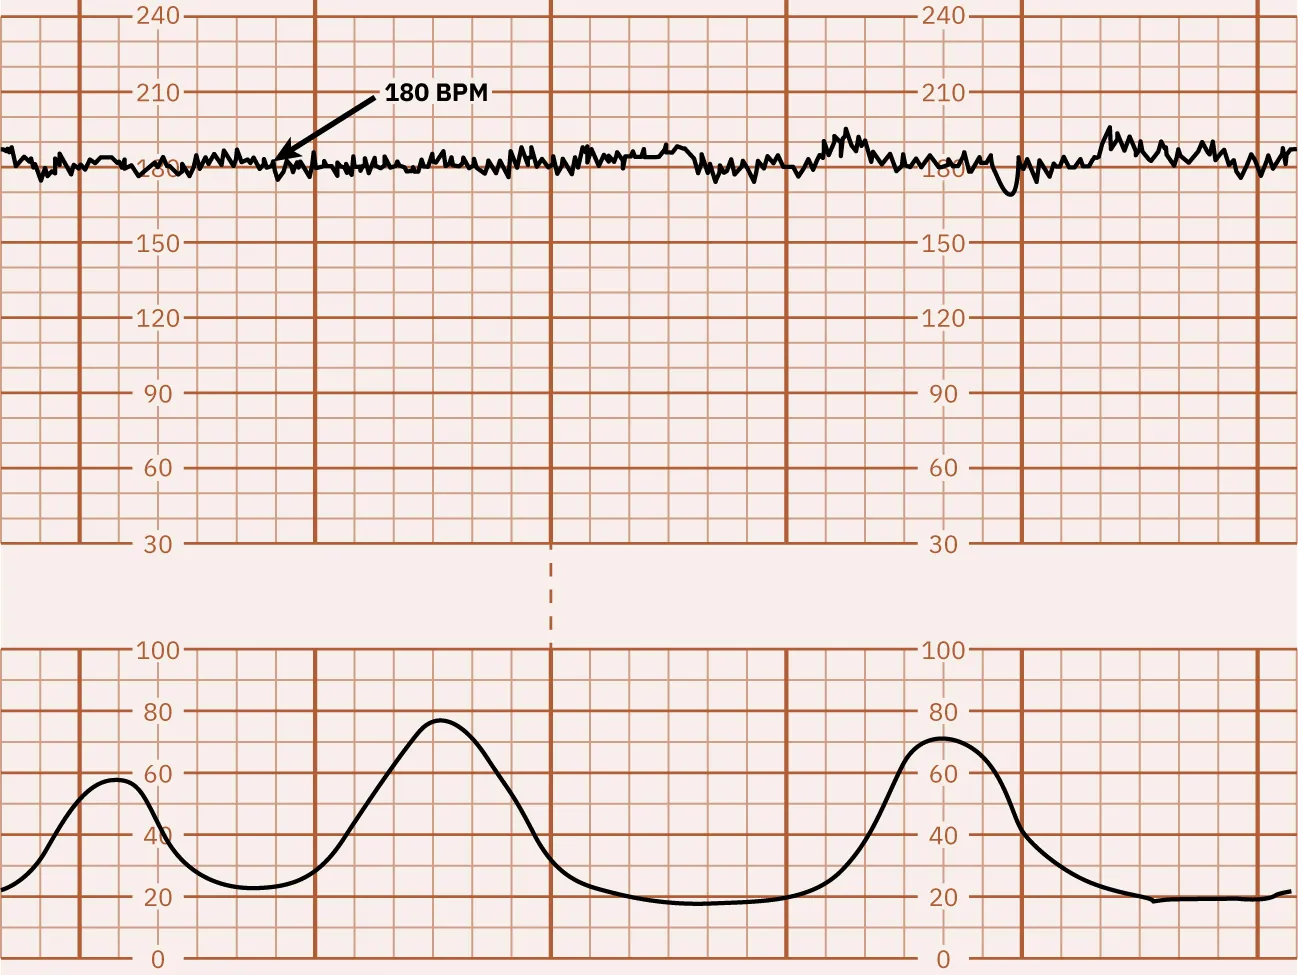

Marked FHR Variability

A FHR baseline fluctuation greater than 25 bpm is considered marked FHR variability. Because of the extreme fluctuations, the FHR baseline is undeterminable. Marked FHR variability suggests hypoxia and is usually seen during the second stage of labor. Marked variability requires further assessment to determine the cause and notification of the health-care provider. Figure 16.8 shows a monitor tracing that indicates marked variability.

Fetal heart rate reading indicating marked variability.

Figure 16.8 Marked FHR Variability This monitor tracing shows marked FHR variability with greater than 25 bpm. (attribution: Copyright Rice University, OpenStax, under CC BY 4.0 license)